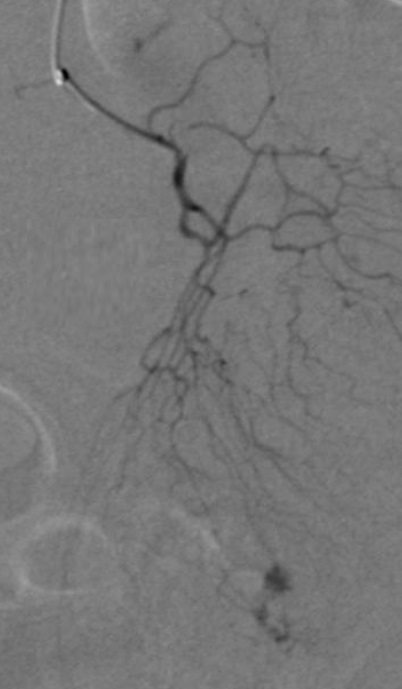

在进行消化道出血栓塞的时候,要考虑病人的情况、临床适应证以及操作者本人的情况。病人的情况包括年龄(不同年龄涉及这是第一次机会还是最后一次机会),抢救性栓塞还是择期栓塞。病人的一般状态包括 Karnovski-,Rankin score,静脉曲张出血时的 MELD score 像结肠或小肠的动静脉畸形的栓塞,有可能是所谓的第一次机会,因为复发或栓塞不全还有第二次机会。就像慢血管静脉畸形的硬化治疗。 78岁 男 急性下消化道大出血

微粒和胶都是可以选择的,但胶更能充分阻塞血管巢,避免侧支循环形成后复发。此病例的另一项选择是经门静脉穿侧选择静脉侧栓塞,可能潜在减少动脉端栓塞的并发症,难度较大。